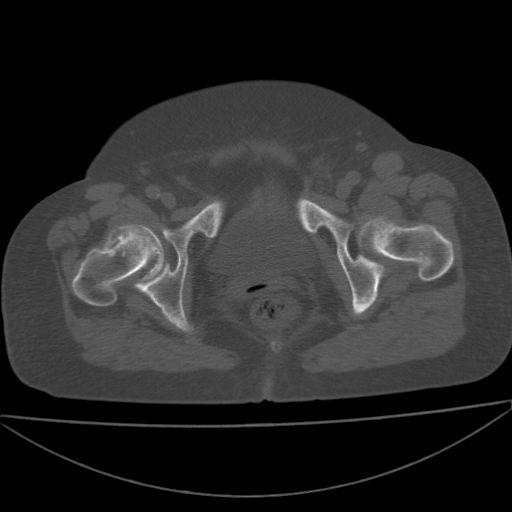

以下是引用余辉在2009-4-23 17:08:00的发言:[br]考虑右髋关节退行性变.股骨颈改变考虑陈旧性骨折可能,股骨头顶部关节面下似有透亮区,股骨头皮质环增厚,考虑有股骨头坏死

以下是引用王显瑞在2009-4-23 16:45:00的发言:[br]考虑股骨颈陈旧性骨折,股骨头缺血型坏死